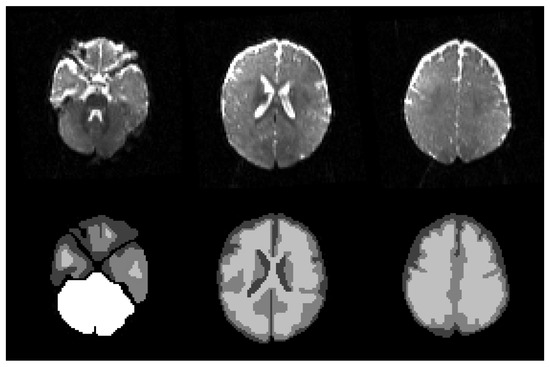

2.3. Extracting the Brain

Segmentation Results